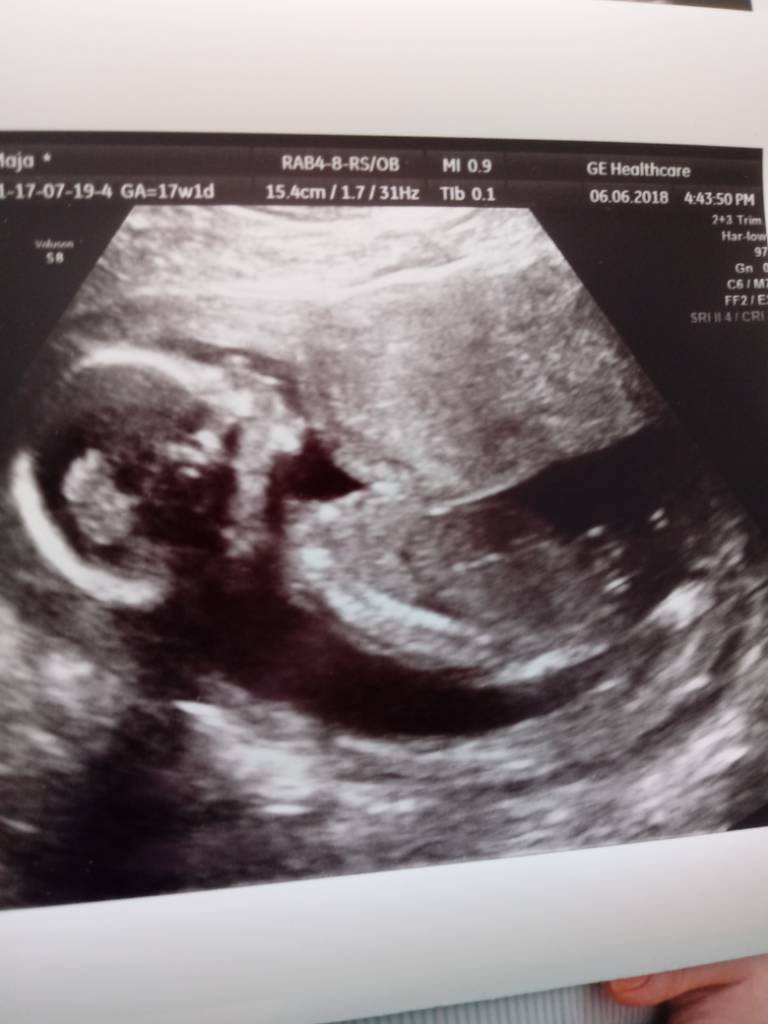

Uwielbiam te zdjęcia 3d. Gratuluję synka.

A na usg dziewczyny idą łeb w łeb z chłopcami 50/50 [emoji4]